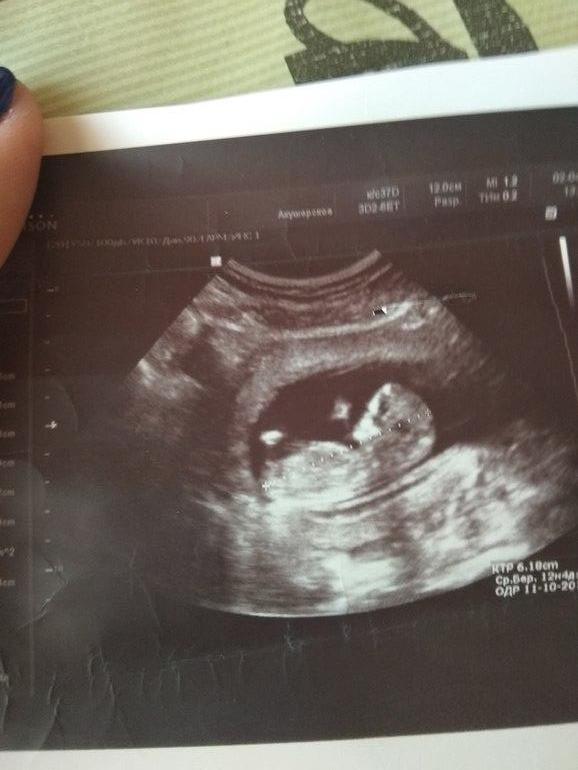

И снова половой бугорок. Сходила ещё раз на узи.

Вот мой Мальчик ,,и бугорок соответственно,,, Срок маленький ,мне в 17 недель мальчика нашли,,а до этого 3 врача девочку предпологали

Похоже на мальчика) я пересмотрела огромное количество бугорков для сравнения на примерно таком же сроке и поняла, что это просто гадание) у нас девчачий горизонтальный бугорок,но у мальчиков тоже такие могут быть вначале и это не редкость. У девочек, как я заметила, реже попадаются бугорки с наклоном вверх. Жду следующее УЗИ, чтобы узнать точно. Розовый кружочек себе поставила, чтобы привыкнуть) почему-то была уверена, что мальчик будет

У моего был наклон даже более горизонтальный, родился мальчик. Тоже кажется, у вас мальчик. Эти бугорки на таком сроке ненадёжные)